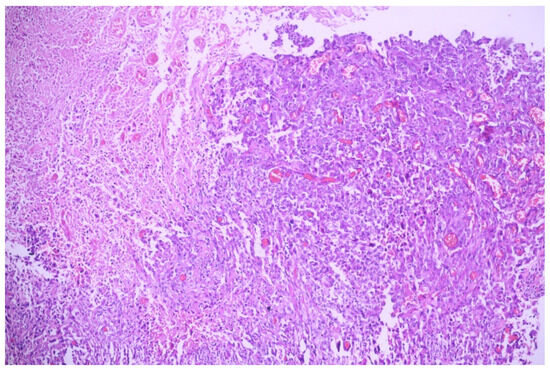

3.1. Case No. 1

3.2. Case No. 2

3.3. Case No. 3

3.4. Case No. 4